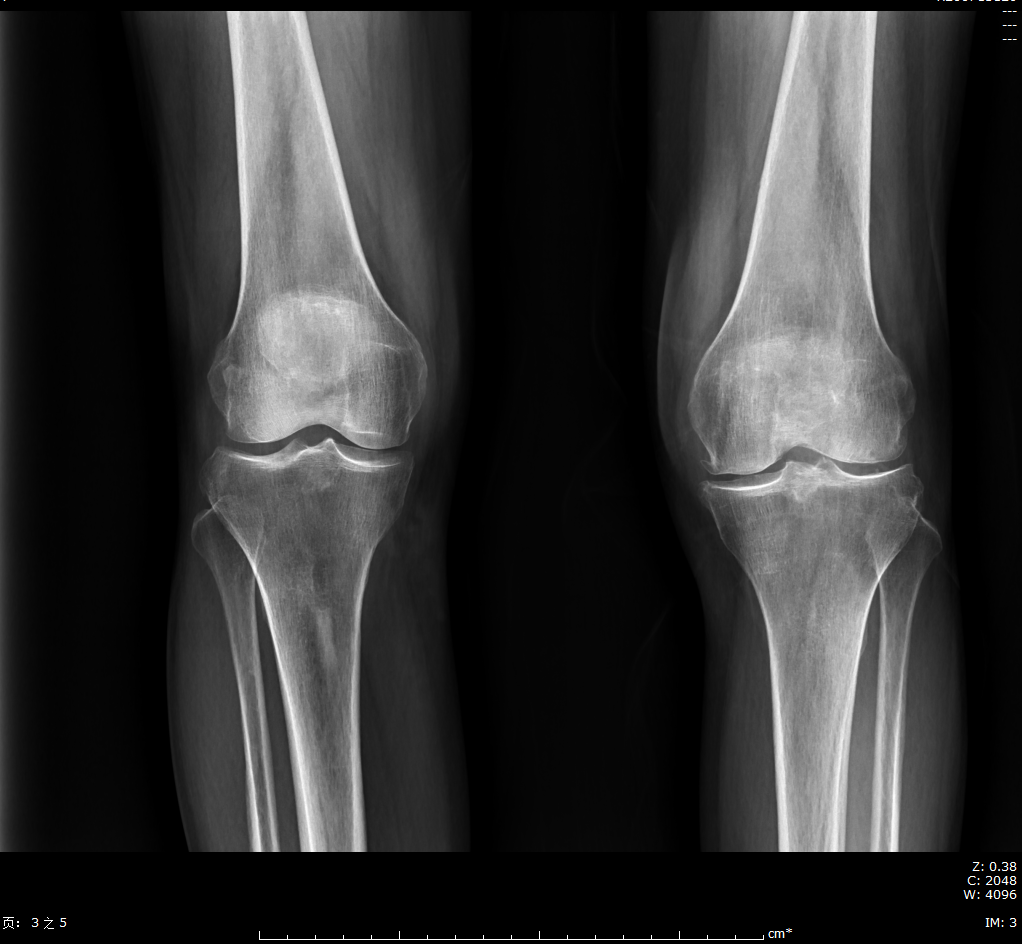

双膝关节X线提示患者右膝关节退行性变,不考虑类风湿关节炎